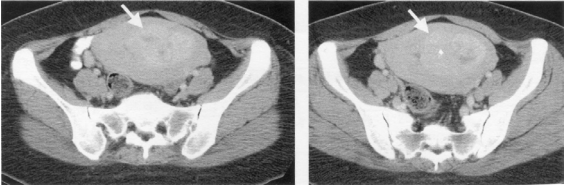

75 40 歲林女士發現數月來月經痛、不規則出血。CT 檢查結果如圖示。林女士最可能患了什麼病?

(A)懷孕(pregnancy) (B)卵巢皮樣囊腫(dermoid cyst) (C)子宮頸癌(uterine cervical cancer) (D)子宮類纖維瘤(uterine fibroid or leiomyoma)